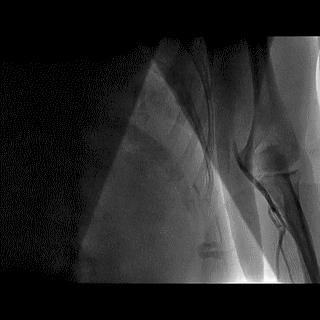

(3)冠状动脉静脉桥血管

首选导管:JR4.0;

其他导管:AL 1.0;AR 1.0

操作:升主动脉造影,寻找静脉桥血管

➢ CASE 3

AL1.0

➢ CASE 4

➢ CASE 5

升主动脉造影未见桥血管显影,原位血管造影也没发现竞争血流迹象,可以确定桥血管已闭塞,必要时可以借助冠脉CTA辅助诊断